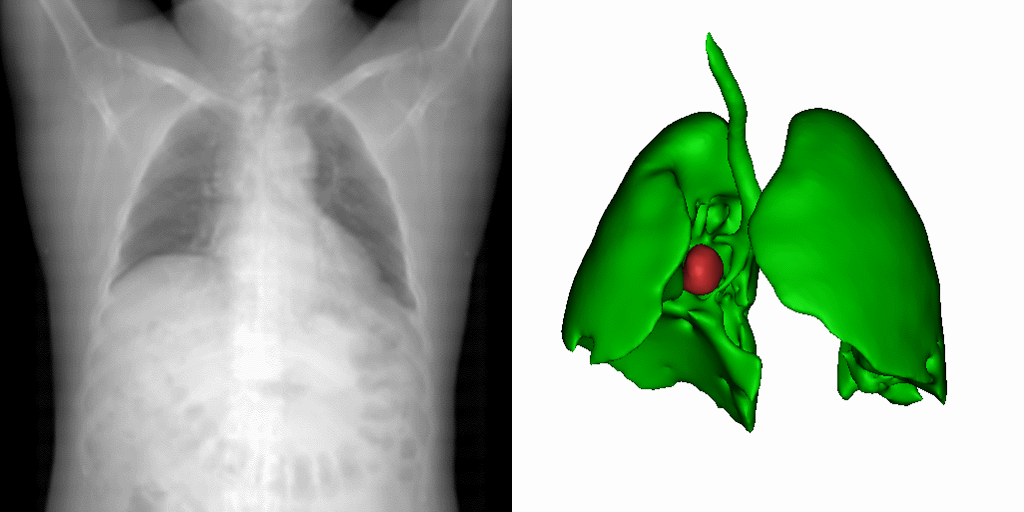

當(dāng)前,深度學(xué)習(xí)在影像引導(dǎo)靶區(qū)定位和分割中的應(yīng)用,多受訓(xùn)練數(shù)據(jù)量的制約。雖然通過優(yōu)化網(wǎng)絡(luò)結(jié)構(gòu)可以在某個(gè)特定任務(wù)上達(dá)到優(yōu)良的性能,但網(wǎng)絡(luò)的泛化性卻受到了犧牲。面對數(shù)據(jù)的稀缺性。研究團(tuán)隊(duì)提出了一種新型的基于統(tǒng)計(jì)形變的三維醫(yī)學(xué)影像數(shù)據(jù)擴(kuò)增法。該方法通過對不同病患的解剖空間變化進(jìn)行建模,以有限的數(shù)據(jù)集中的形態(tài)信息,產(chǎn)生物理上真實(shí)反映病患器官變化的圖像。如圖1所示,一幅原始病患影像,經(jīng)過此形變模型處理,便可衍生出多種器官的解剖結(jié)構(gòu)。在多個(gè)公開數(shù)據(jù)集的實(shí)驗(yàn)中,這一方法展現(xiàn)了最好的靶區(qū)定位與分割效能。研究成果以A statistical deformation model-based data augmentation method for volumetric medical image segmentation為題,發(fā)表在醫(yī)學(xué)影像分析頂刊Medical Image Analysis (IF=10.9)??妥究粕挝呢S為第一作者,梁曉坤副研究員為通訊作者。

圖1:研究團(tuán)隊(duì)提出的基于統(tǒng)計(jì)形變模型的三維醫(yī)學(xué)影像數(shù)據(jù)擴(kuò)增法的實(shí)現(xiàn)效果